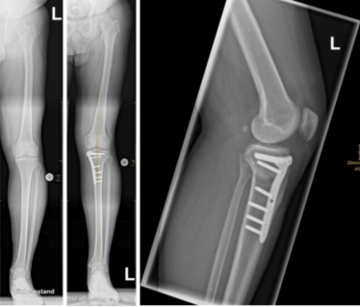

Patient vor und nach Umstellungsoperation am Scheinbein (aufklappende Tibiakopfosteotomie bei O-Bein)

Der häufigste Grund für eine Umstellungsosteotomie ist entsprechend der beginnende oder vorhandene Verschleiß eines Anteiles des Kniegelenks bei bestehender Achsfehlstellung des betroffenen Beines. Die korrigierende Osteotomie kann durch Entfernung eines Knochenkeiles (zuklappende Osteotomie, closed-wedge) oder durch eine Aufspreizung des Knochens (aufklappende Osteotomie, open-wedge) erfolgen. Ziel der Umstellungsosteotomie ist es, die geschädigte Gelenkregion durch eine Korrektur der Fehlstellung zu entlasten. Dabei wird die Beanspruchung des Gelenkes in Richtung der zu erhaltenden Gelenkregion verlagert. Hierfür erfolgt ein operatives Durchtrennen des Schienbein- oder Oberschenkelknochens (Osteotomie), in Abhängigkeit der vorliegenden Fehlstellung. Die Osteotomie wird dann über winkelstabile Plattensysteme aus Titan in der korrigierten Position gehalten, bis eine sichere Knochenheilung erfolgt ist. Eine Ruhigstellungen im Gips ist nach der Operation nicht erforderlich.